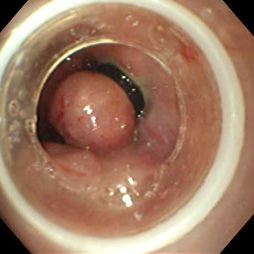

食管靜脈瘤呈青藍色或紫藍色圓形或卵圓形扁平狀隆起,表面黏膜完好,無新近或陳舊性出血灶,無搏動,邊界清楚,如無食管合併症,則周圍食管黏膜無異常;如靜脈瘤為多發性,則各個靜脈瘤之間有正常食管黏膜間隔而非連續性;如與食管靜脈曲張並存,其間也間隔有正常食管黏膜;食管靜脈瘤無出血、潰瘍、癌變等,也不引起食管解剖或功能性狹窄,屬良性病變。

一般使用內鏡診察,此外還可進行CT診察、超聲內鏡診察(Endoscopicultrasonography:EUS),以觀察其引起出血的可能性、詳細狀態、判斷治療效果等。通過內鏡診察來觀察食管靜脈瘤的出血、糜爛以及周圍的血管等,並以此決定治療方針。